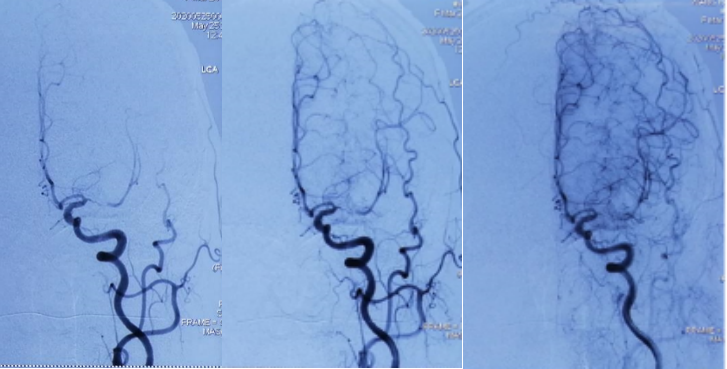

术中造影

DSA(天坛医院-2021.03.17 MCA支架内重度狭窄

赛诺球囊扩张(1.5 mm×15 mm)

赛诺球囊扩张后狭窄有所改善但管壁不光滑

药物球囊扩张(2.0 mm×20 mm)

药物球囊扩张后

药物球囊扩张后10分钟狭窄明显改善且血管壁较光滑